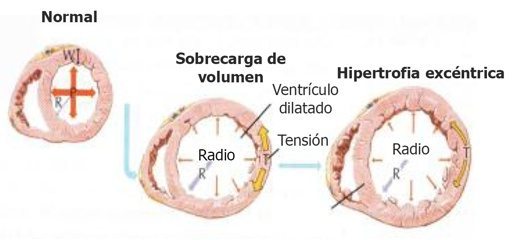

Alteraciones macroscópicas:

- El corazón suele estar agrandado, pesa más y tiene una consistencia blanda, debido a la dilatación de todas las cavidades.

- Los trombos parietales son frecuentes y son una fuente posible de émbolos.

- No existen alteraciones valvulares primarias, y cuando hay insuficiencia mitral (o tricuspídea), se relaciona con la dilatación sufrida por la cavidad ventricular.